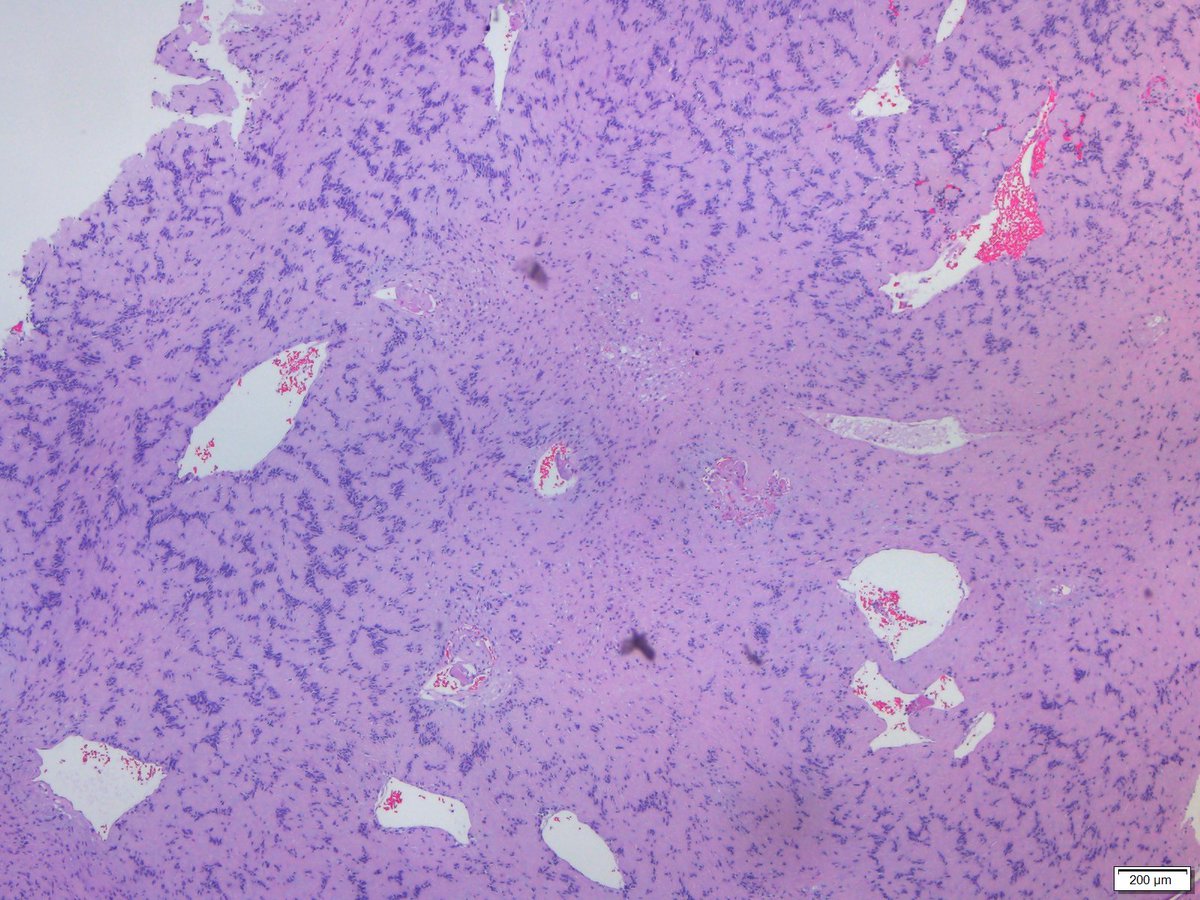

@ATchakarov1

A Tchakarov

10 months

Usually when I get a renal biopsy for proteinuria in a diabetic patient, it ends up being diabetic nephropathy...but sometimes there's something else going on. 👀🔬 #RenalPath #Nephropath #Nephrology #PathX #PathTwitter